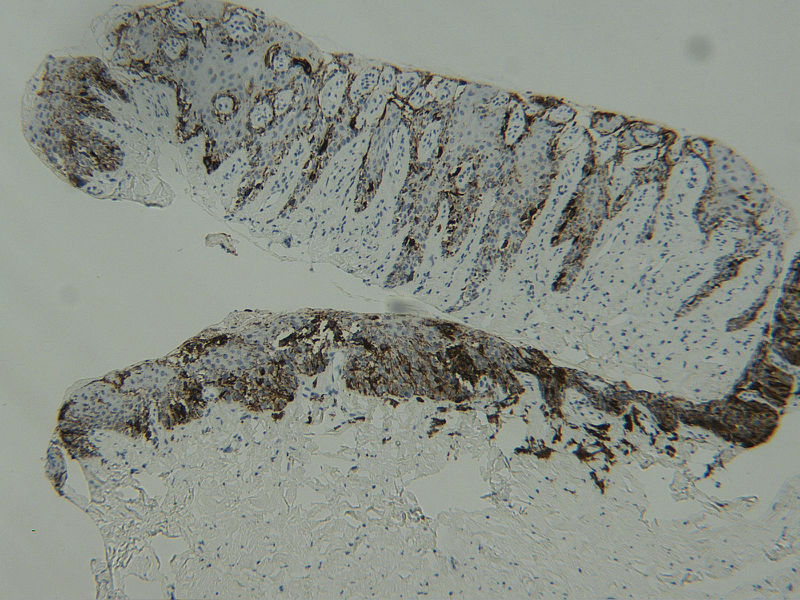

图1HMB45

女 68岁 右手拇指甲变黑及扩散2年,无自觉症状,有风湿性关节炎病史数年。